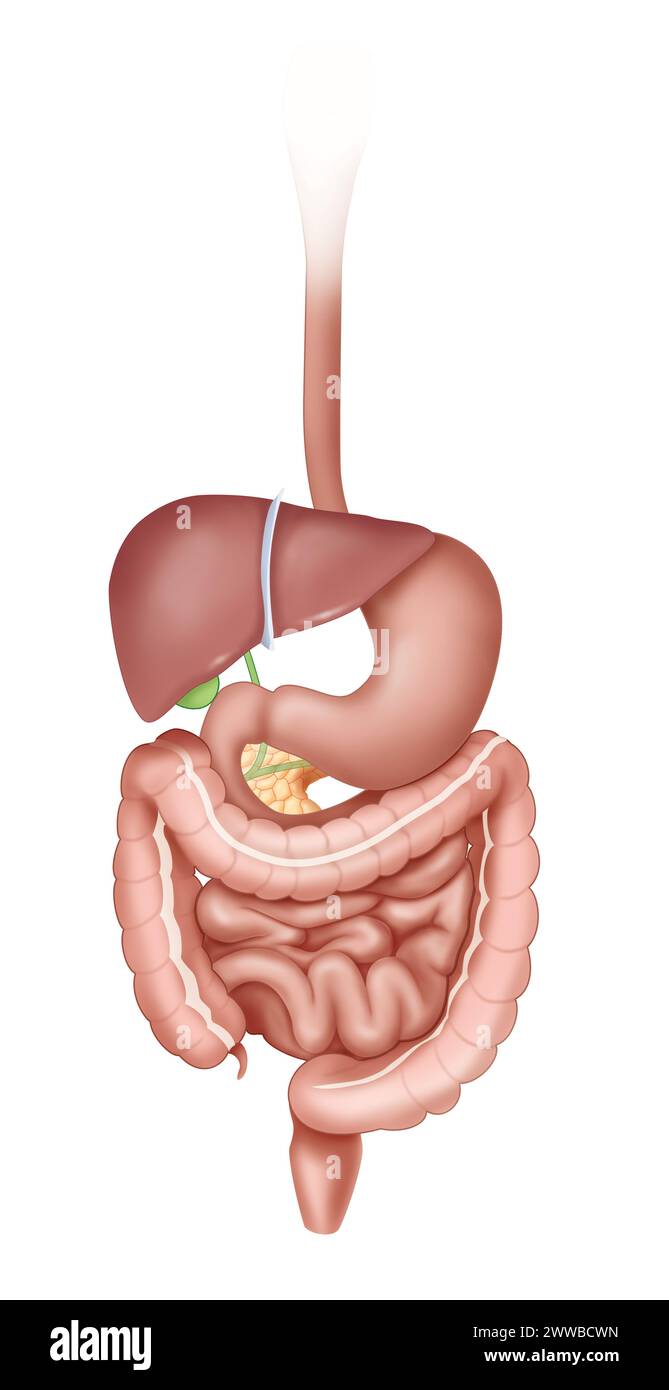

RM2WWBCW9–Reins en vue antérieure avec uretères surrénaliennes et artères et veines rénales. Le rein gauche est placé plus haut que le rein droit.